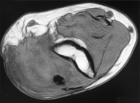

77 year old WM with one year history of right elbow mass with ulceration of the skin, tingling in right small finger also noted

Zoom image: Radiological image Radiological image.